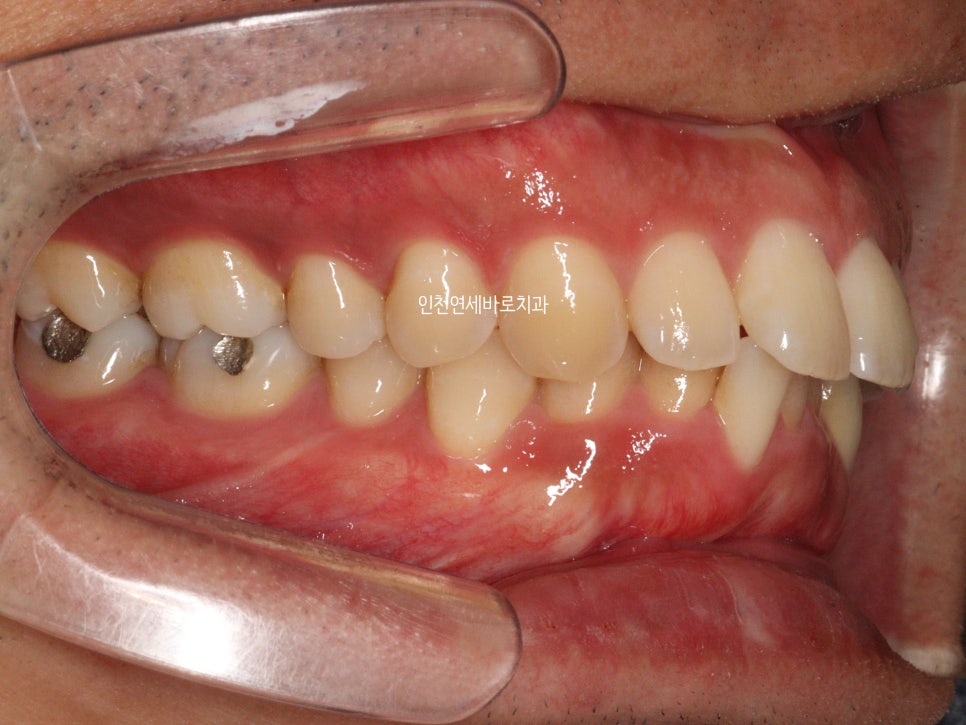

앞니가 뻗쳐있고, 아래치아가 안보이고

덧니가 심해서 내원한 환자분입니다

치료 전과 후의 비교입니다.

교합도 양호하게 마무리.

악궁의 확장을 통한 앞니의 후방이동도 최대한 이루어냈습니다.